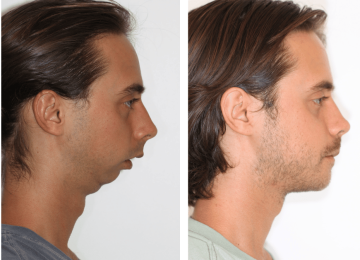

Desconforto funcional na região orofacial, associado a dificuldades mastigatórias e episódios recorrentes de dor

A atuação em cirurgias da face exige formação especializada, experiência clínica e uma abordagem integrada entre Odontologia e Medicina.

Somos especialistas no tratamento e cirurgia do rosto, maxilares, boca e estruturas da cabeça e pescoço.com atuação tanto em consultório quanto em ambiente hospitalar.